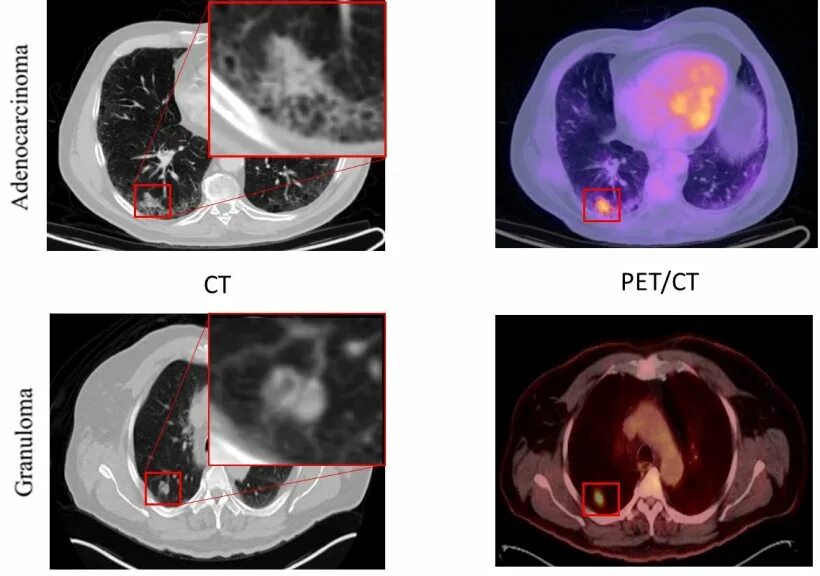

Рак прямой кт